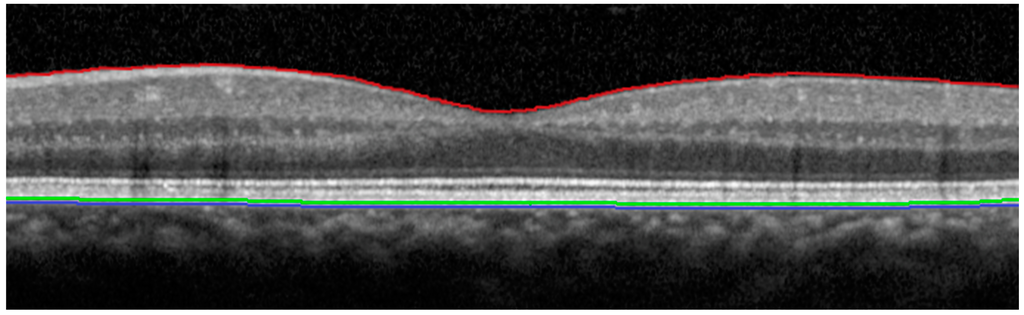

Figure 1.

OCT scan from a healthy subject, demonstrating the different retinal layers that are used to define the outer retinal border for each SD-OCT device. Red line: Vitreo-retinal interface. Green line: Outermost retinal border defined by the Spectral OCT/ SLO (Optos plc, Dunfermline, Scotland, UK). Blue line: Outermost retinal border defined by the Spectralis HRA + OCT (Heidelberg Engineering, Heidelberg, Germany).

Two previously published studies that compared macular retinal thickness measurements between the Optos Spectral OCT/SLO and Heidelberg Spectralis HRA + OCT [16,18] did not analyse the correlation between the two devices. They were both conducted in healthy subjects and Wolf-Schnurrbusch et al. [16] only analysed the central retinal thickness in the 1 mm area around the fovea; however, similar to our study, they also reported higher retinal thickness measurements with the Heidelberg Spectralis HRA + OCT compared to the Optos Spectral OCT/SLO. Whilst their central retinal thickness measurements revealed a 45 µm [16] and 57–60 µm [18] difference between the devices, our study found a difference of 73 µm in the central zone and 43–50 µm in the parafoveal zones. These studies [16,18] have proposed that as both devices use different software for segmentation of the outer retinal border, with the Spectralis HRA + OCT identifying a deeper reflective border as the outermost retina, then this result is not entirely unexpected; whilst the Heidelberg Spectralis HRA + OCT measures retinal thickness between the vitreo-retinal interface and the outermost reflective band of the RPE, the Spectral OCT/SLO measures retinal thickness to the mid-RPE reflectance instead (Figure 1). Other studies have also proposed this as a cause for the differences between macular thickness measurements when comparing other OCT devices [17,19,21,22,24,25]. However, there may also be a variety of other factors influencing macular thickness measurements between the devices, in addition to differences in defining segmentation algorithms. For example, devices may also differ in their scan patterns and methods of signal collection [16,18,19,22,25], tracking and axial resolution [18,19,25], optics [16], and imaging processing software algorithms [16,18,19,25]. Unlike Wolf-Schnurrbusch et al. [16] and other studies [19,22], we measured the retinal thickness for the central circle and four parafoveal zones, encompassing the central 3.0 mm around the fovea. This is because the normal anatomy of the retina involves a gradual increase in thickness as the distance from the fovea increases; as such, a single foveal measurement would depend more greatly upon accurate centration than the totality of an area of 3.0 mm around the fovea.

The retinal thickness was determined for the central circle and the four parafoveal zones of the inner ring for both devices (Figure 2 and Figure 3), measuring the central 3.0 mm around the fovea. For the Heidelberg Spectralis HRA + OCT, retinal thickness was the distance between the vitreo-retinal interface and the outermost reflective band of the retinal pigment epithelium (RPE). For the Spectral OCT/SLO, retinal thickness was defined as the distance between the vitreo-retinal interface and the mid-RPE reflectance (Figure 1).